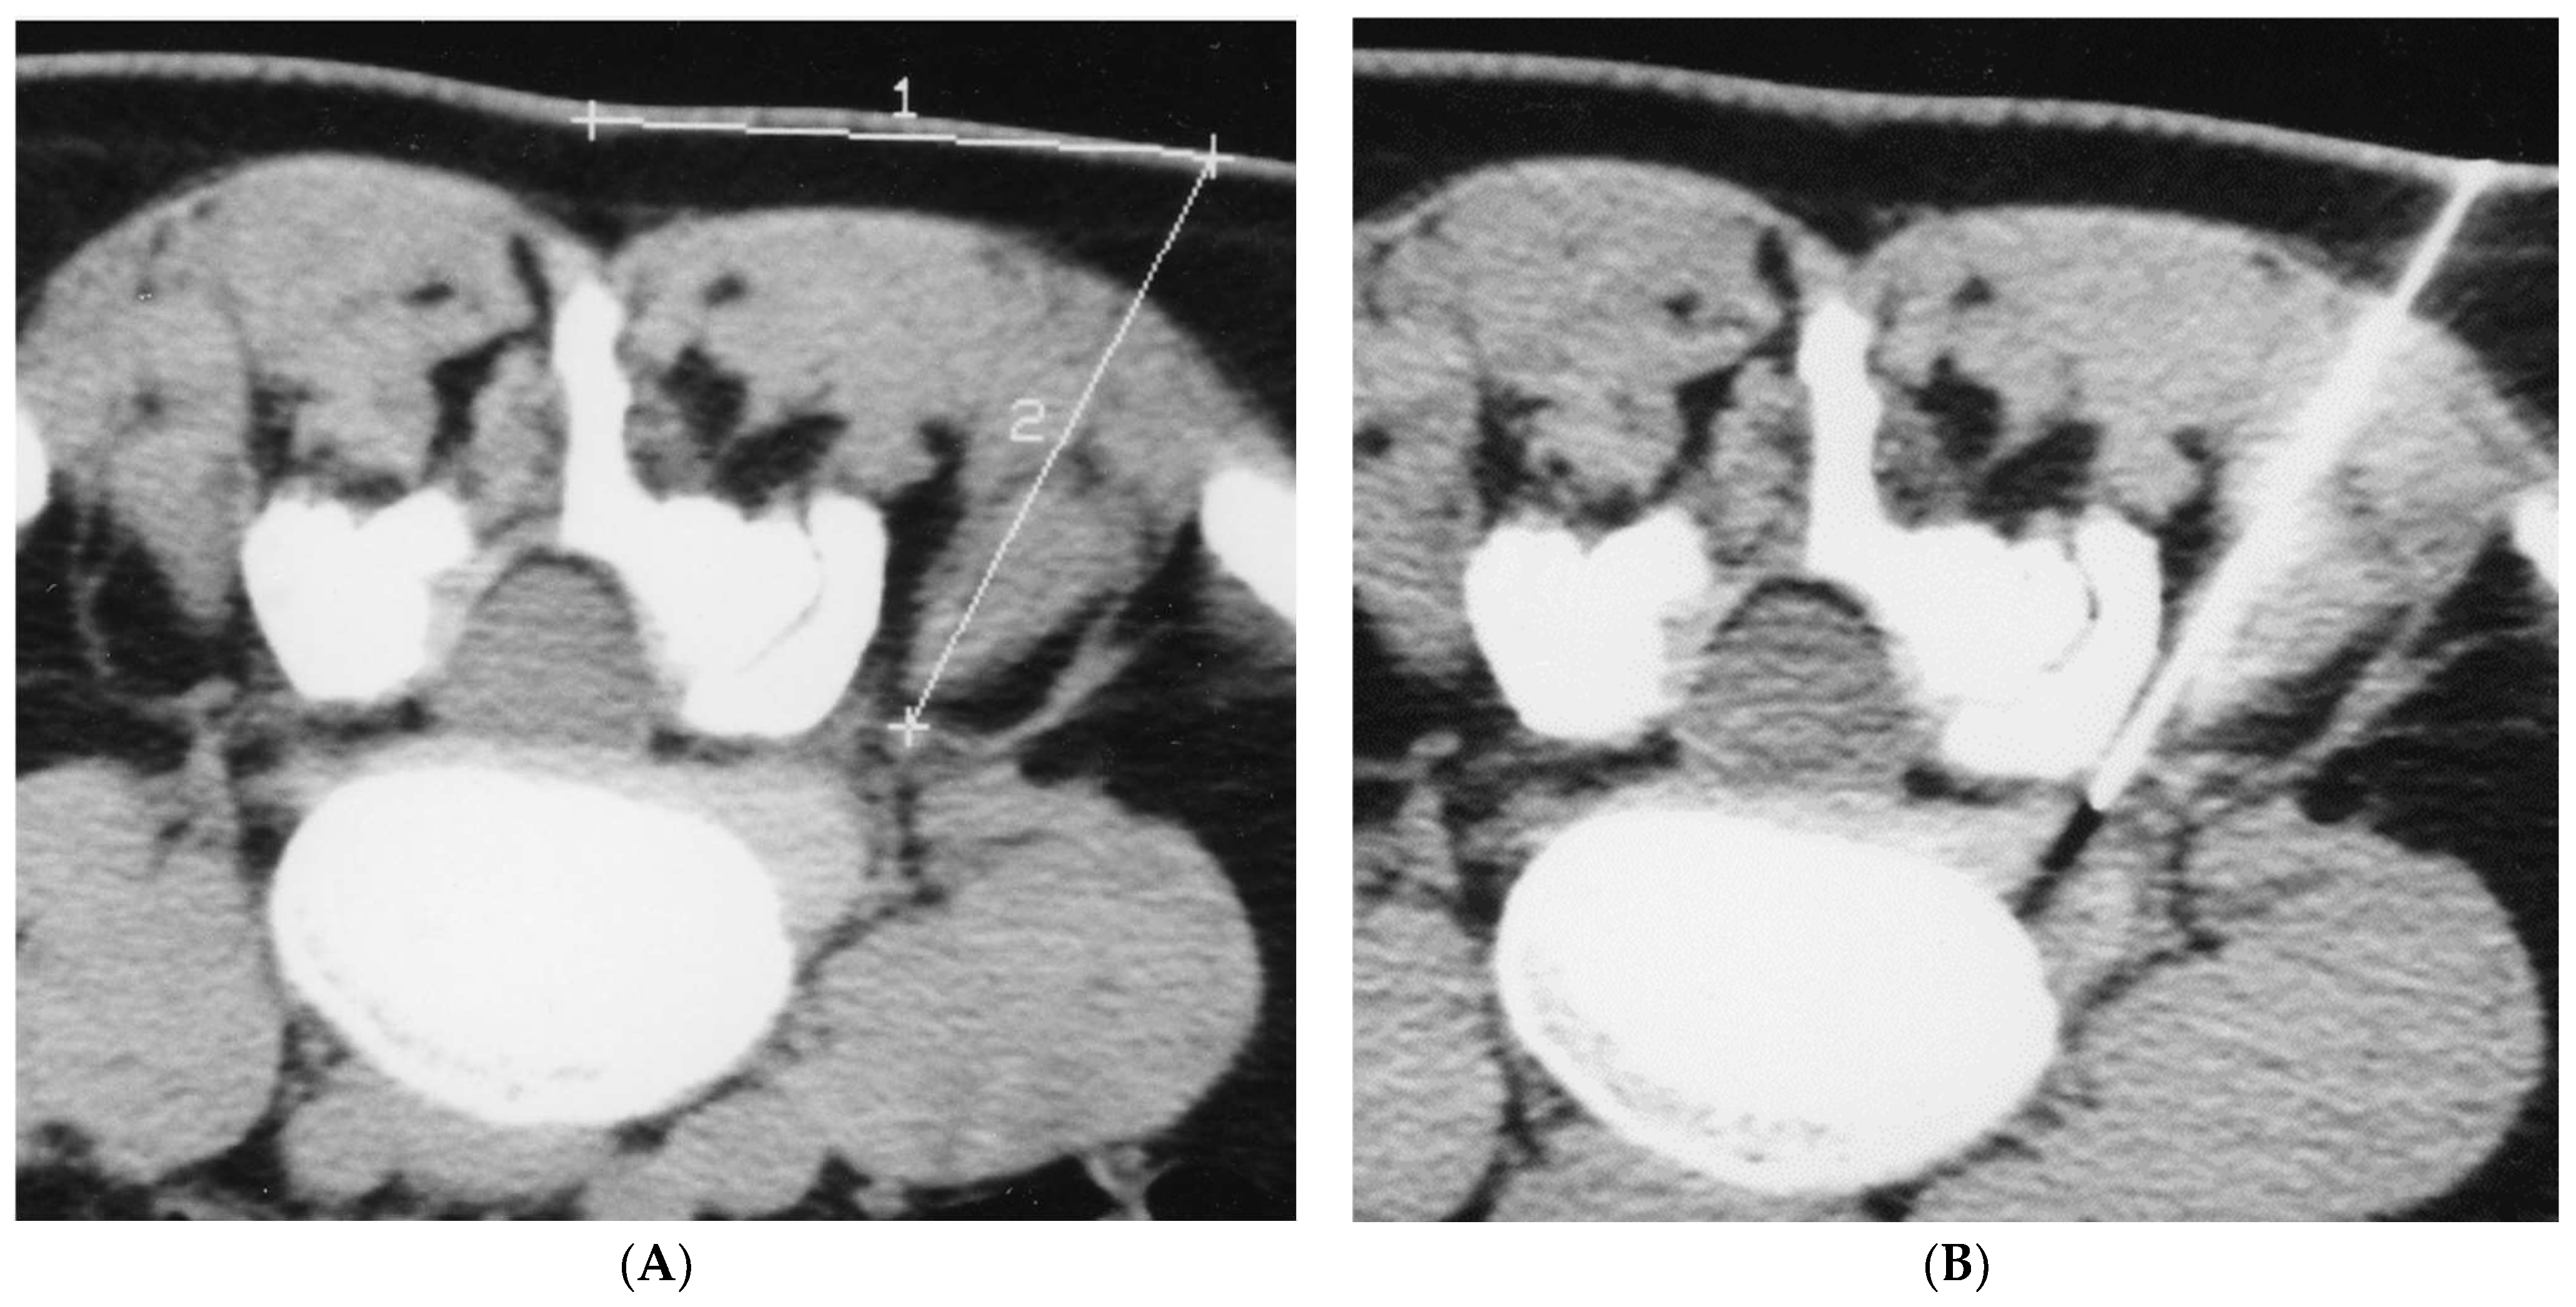

2.1. Infiltration Technique